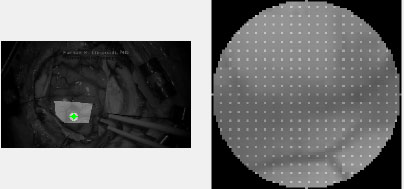

After the ROI is chosen, subset options must be selected. The two most important options are subset spacing and subset radius. These determine the “accuracy” of the DIC analysis as well as the computational load. Specifically, an increase in the subset spacing decreases the computation load but creates larger segments. This can negatively impact spatial resolution of the DIC analysis [5, 11]. Additionally, increasing subset radius improves pattern recognition and decreases the risk of generating artefactual data or noise. This occurs at the “cost” of spatial resolution [12]. A visualization of a subset can be seen in Fig. (3).

Lastly, Ncorr requires the user to place “seeds.” These are selected points within the ROI which provide initial guesses for the DIC algorithms. Seeds also partition the ROIs for multithreaded processing. In effect, seed placement allows the user to create subsections for analysis.

An example of seed placement is shown in Fig. (4). These initial guesses allow users to identify suboptimal seed placement, which may lead to inaccurate DIC analysis. For example, suboptimal placement may lead to the seed leaving the ROI entirely. This would potentially generate inaccurate displacement analysis.

Furthermore, the number of seeds is determined by the number of available CPU cores. Thus, more CPU cores will allow for greater computational speed. Additionally, excessive discontinuity between frames may result in a loss of pixels. This often happens near regions of heavy movement or reflective glare.

However, samples with sufficient “natural” textures may not require artificial patterning [13]. The network of blood vessels, sulci, and gyri which are visible on the brain’s surface, proved sufficient for Ncorr’s processing. This was verified by utilizing a mock craniotomy model which is illustrated in Fig. (5).

Note that a hole was cut into a plastic skull, and a water-filled balloon was then used to model the surface of the brain. Artifacts, in the form of geometric or random lines, were then drawn onto the balloon’s surface. The balloon was subsequently filled with increasing amounts of water (e.g., 30, 40, 50 mL). Ncorr then determined surface displacement. Manual measurements were also simultaneously obtained by means of a digital calliper. Microsoft Excel was then utilized to perform Spearman’s correlation tests to verify the accuracy of Ncorr.